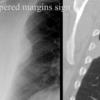

Tapered margins sign

Pleural or extrapleural origin

Tapererd margins sign

Pleural lipoma